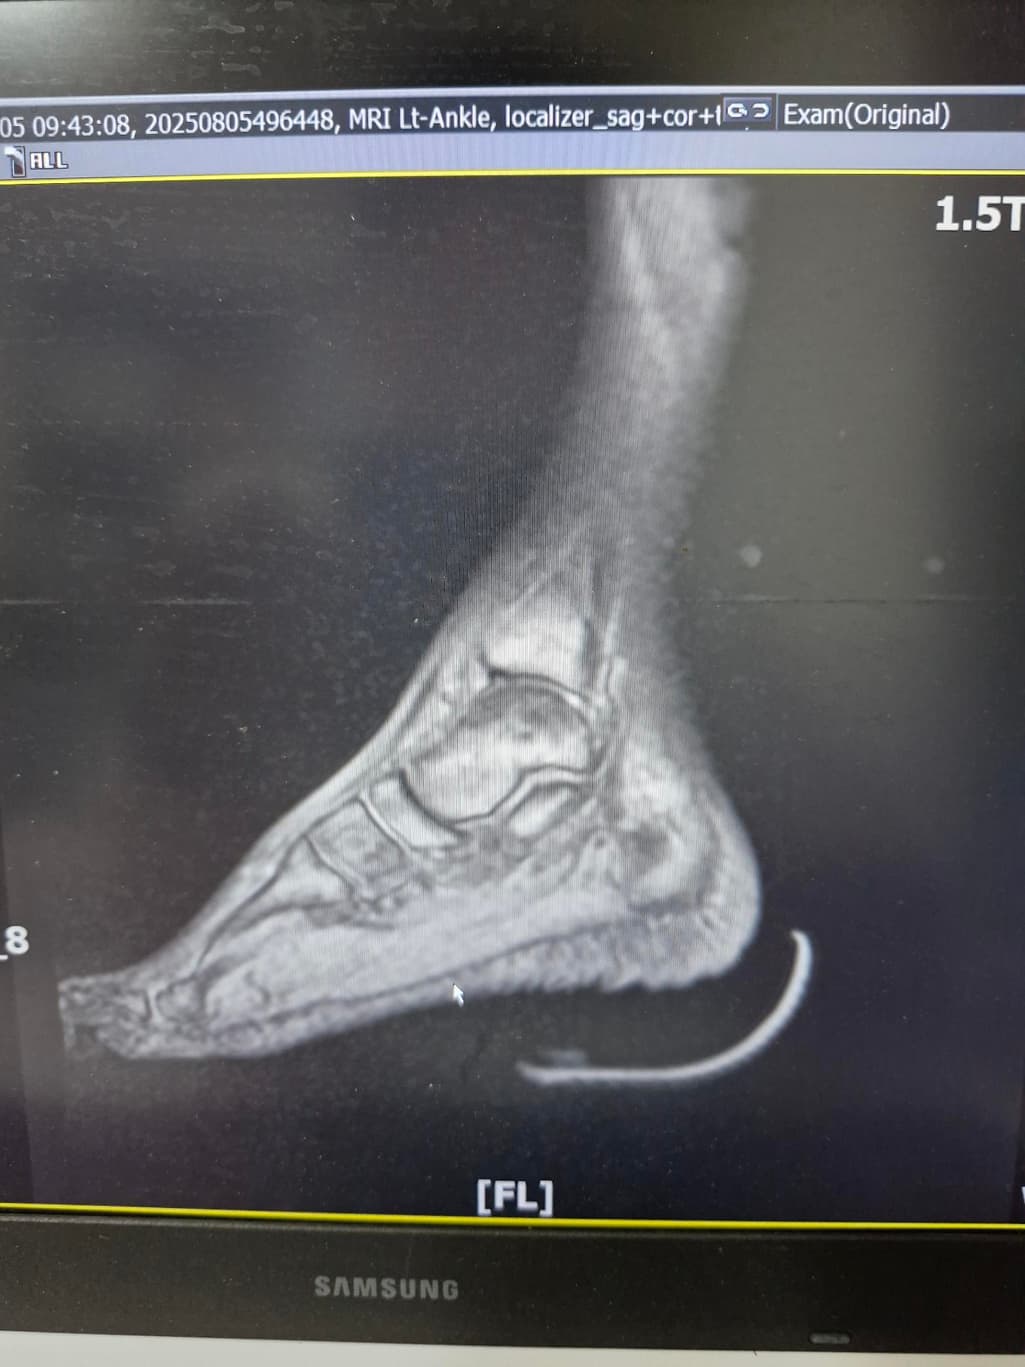

그래도 통증이 남아 8월 5일에 MRI를 촬영했는데, 병원에서는 “인대는 이어져 있고, 이 정도면 재활운동으로 호전될 것”이라는 설명을 들었습니다.

MRI 상 전거비인대와 발목 상태가 정말 회복 단계인지, 아니면 만성으로 넘어가는 건 아닌지 전문가분들의

의견을 듣고 싶습니다.

올려주신 mri를 보면 전거비인대는 연속성이 유지되고 있고 파열이나 큰 손상 흔적은 없어 재활로 회복 가능한 상태로 보입니다 다만 3개월 가까이 활동 시 통증과 미열감이 남아 있는 것은 조직 회복이 아직 완전히 끝나지 않았거나 주변 연부조직 관절 움직임 제한 등으로 인한 과민 반응일 수 있습니다.

초음파와 비교하면 mri 상으로 인대 연속성이 확인되므로 심각한 악화나 재파열은 아닌 것으로 판단됩니다